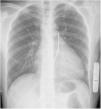

Clinical caseWe report the case of a 17-year-old federated soccer player who sought emergency care following an episode of palpitations and dizziness while playing soccer. He reported having already had two episodes of syncope upon exertion in the last six months but did not value them and therefore did not go to the emergency room. He denied any other personal history, regular consumption of drugs or narcotics and any relevant family history, including a history of SCD. The patient was tachycardic (218 bpm) and hypotensive (85/56 mmHg). A 12-lead ECG was performed which revealed wide complex tachycardia with left bundle branch block morphology and superior axis (Figure 1). Given the hemodynamic instability, the patient underwent electrical cardioversion with a biphasic shock of 50 joules and reverted to sinus rhythm. The ECG in sinus rhythm showed a T-wave inversion of V1–V5, with no other alterations (Figure 1). From laboratory tests, only a slight elevation of troponin I (0.97 ng/ml) was noteworthy. A transthoracic echocardiogram showed a non-dilated LV with good global systolic function, slight RV dilation and slight depression of its function (FAC) of 29%), with no other changes (Figure 2). The patient was hospitalized and underwent cardiac magnetic resonance imaging (CMR). CMR showed marked RV dilatation (end-diastolic volume indexed to body surface area of 180 ml/m2) by global hypokinesis with mild depression of its function (42%) and desynchrony. The late enhancement images showed subepicardial late enhancement in the distal septum and two small foci of subepicardial late enhancement in the middle segment of the inferoseptal wall (Figure 3). Thus, according to the 2010 TFC for the diagnosis of ARVC, the patient had three major criteria for the diagnosis of ARVC, including morphofunctional changes (areas of hypocontractility with a FAC ≤33%; desynchrony and RV end-diastolic volume indexed to body surface area ≥110 ml/m2), repolarization changes (inverted T-wave of V1–V5 in the absence of criteria for complete right bundle branch block), arrhythmia (sustained ventricular tachycardia with LBBB morphology and superior axis). Thus, taking into account that only two major criteria are needed for its diagnosis, the diagnosis of ARVC was made. Also, during hospitalization, the patient was implanted with a subcutaneous cardioverter-defibrillator (Figure 4). The patient remained asymptomatic throughout hospitalization. He was discharged with low-dose beta-blocker medication and contraindication for practicing sports. He is in regular follow-up in the Cardiology consultation, and adheres to the prescribed medication and recommendations, having, to date, no record of any new arrhythmic events. During follow-up, a genetic test was requested and enabled the identification of a pathogenic mutation categorized as associated to ARVC – variant c.1044_104dupAAAT (p.Asp350Lysfs*2) in the DSC2 gene which encodes the desmocholine-2 protein, and is implicated in the pathogenesis of ARVC. Thus, the patient has four major diagnostic criteria. A Holter was also requested which showed a number of ventricular extrasystoles >500 per day, fulfilling a minor criterion for the diagnosis. Currently, the patient does not participate in high-level sports nor any type of recreational sport.